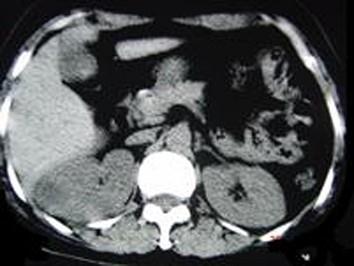

问题 女,12岁,右腰部疼痛10天,尿检可见大量的脓细胞 CT平扫+增强如图所示,应诊断为 ( )

选项 A、右侧肾癌 B、右肾结核 C、右侧感染性肾囊肿 D、右肾转移瘤 E、右肾脓肿

答案 E